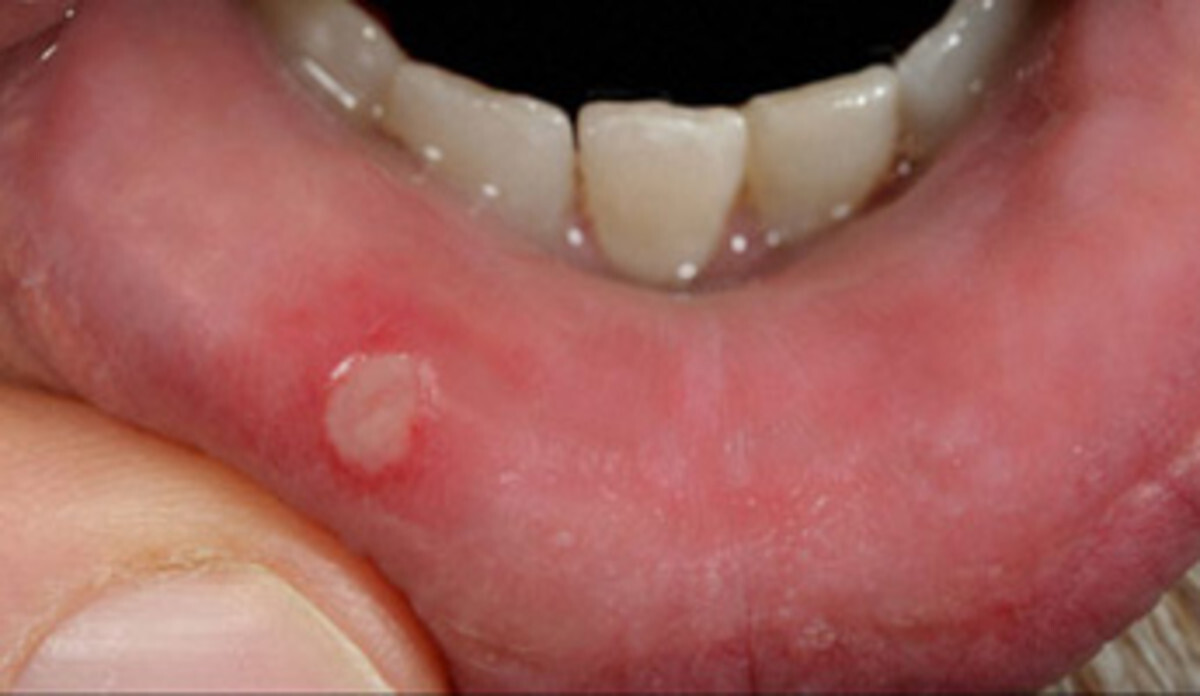

Ulcerative colitis can also affect the oral mucosa, the soft tissue inside your mouth on your gums and cheeks. Two types of ulcerative colitis mouth ulcers exist:

Aphthous ulcerations. Also known as canker sores, these lesions appear as round white or yellow spots and can cause pain or bad breath. You are more likely to experience canker sores during ulcerative colitis flare-ups when inflammation is higher. They can take a week or more to heal.